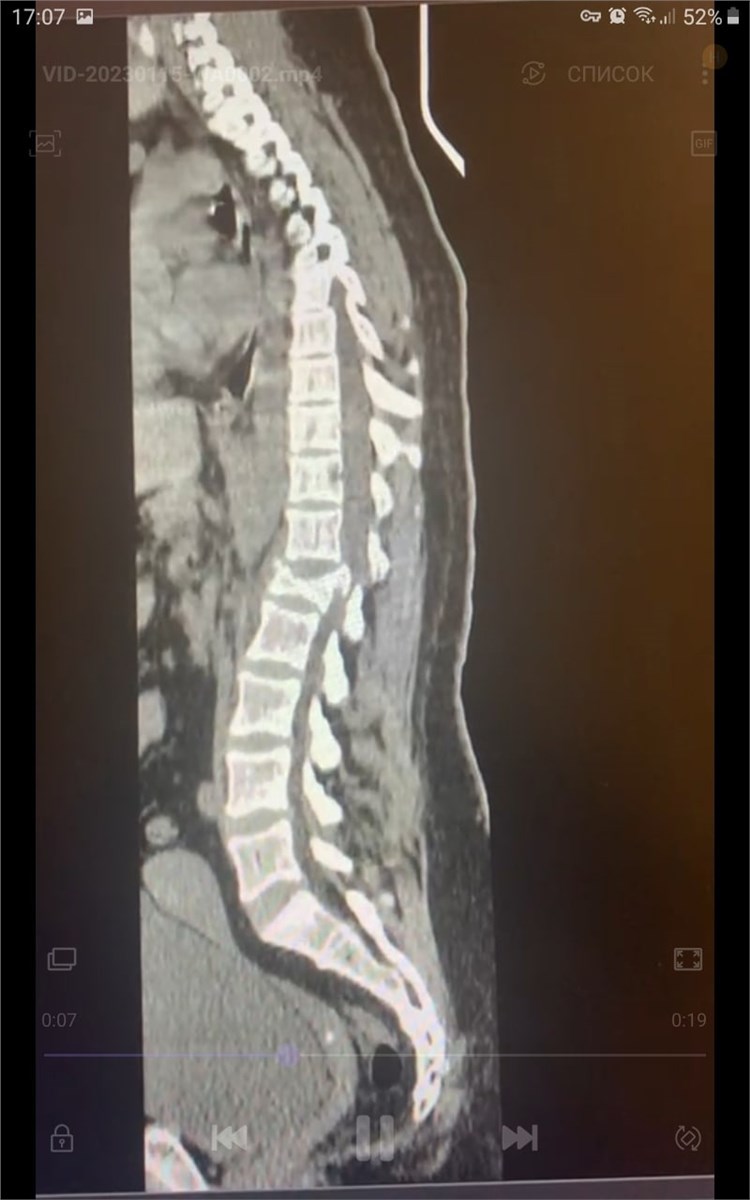

В Красноярске врачи БСМП прооперировали молодую женщину, которая получила серьезную травму позвоночника во время спуска с горы на тюбинге.

В  Красноярске врачи БСМП прооперировали молодую женщину, которая получила серьезную травму позвоночника во  время спуска с  горы на  тюбинге. Пострадавшая на  скорости выпала из  «плюшки».

Оперативное лечение женщины проходило в  несколько этапов. Травматологи в  месте травмы зафиксировали позвонки при помощи специальных имплантов